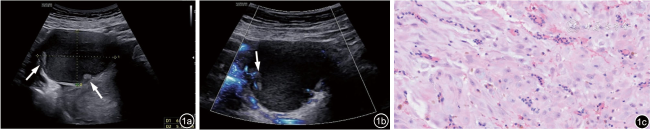

1.病例1:患者29岁,病史不详。此次停经38 d,未诉不适。超声检查提示宫内早孕,右侧卵巢一囊性结构,大小约6.9 cm×5.2 cm×6.4 cm,内透声差,囊壁可见数枚乳头样突起,大者约0.5 cm×0.4 cm(图1a),彩色多普勒血流显像(color Doppler flow imaging,CDFI)示乳头内可见血流信号(图1b),子宫滑动征阴性。分别于停经6+、12+、21+、22+、28+、30+、35+、37+、38+、39+、40+周继续复查右侧卵巢囊性结构(共12次),4次提示OEM可能性大,囊壁不规则增厚伴乳头形成,8次提示为囊腺瘤不除外,囊肿大小无显著变化,乳头状突起大小及形态变化不明显,CDFI示乳头内可见少许血流信号,阻力指数(resistance index,RI)为0.56。该患者实验室检查示孕期糖类抗原125(carbohydrate antigen 125,CA125)为50.44~125.6 U/ml(正常范围:<35 U/ml),22+周甲胎蛋白为84.6 ng/ml(正常范围:<20 ng/ml)。于22+周因CA125、CA724及甲胎蛋白升高行超声检查,提示OEM可能性大,囊壁不规则增厚伴乳头形成。因可疑卵巢交界性肿瘤,经妇科专家会诊并告知手术风险和病情后,孕妇仍然要求继续妊娠,观察随访。于妊娠40+周行子宫下段剖宫产术+右侧卵巢囊肿剥除术,术中探查子宫底及子宫右后壁与右侧阔韧带呈蔓状粘连,卵巢囊肿囊壁内面粗糙,见多发乳头,分离过程中囊肿破裂,可见巧克力样黏稠液体流出,量约150 ml。术后病理诊断为子宫内膜异位囊肿,间质蜕膜样变(图1c)。术后恢复良好。

图1 停经38 d,右侧附件肿块经阴道超声图像。图a为灰阶超声显示右侧卵巢一囊性为主的混合回声(箭头示囊内实性乳头状突起);图b为彩色多普勒超声显示囊内实性乳头状突起内可见少许血流信号(箭头示囊内实性乳头状突起处血流信号);图c为病理示卵巢子宫内膜异位囊肿并间质蜕膜化(HE ×200)